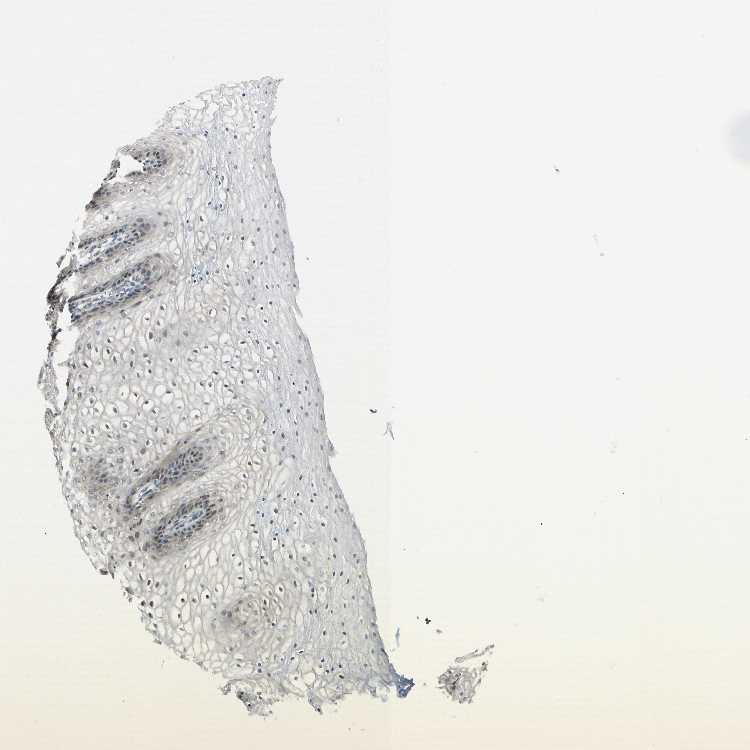

TISSUE PRIMARY DATA VAGINA Show tissue menu

VAGINA - Antibody stainingi

Antibody staining in the annotated cell types in the current human tissue is reported as not detected, low, medium, or high, based on conventional immunohistochemistry profiling in selected tissues. This score is based on the combination of the staining intensity and fraction of stained cells.

Each image is clickable and will lead to virtual microscopy that enables deeper exploration of all samples and also displays staining intensity scores, fraction scores and subcellular localization as well as patient and tissue information for each sample.

Antibody HPA008189

Squamous epithelial cells Low